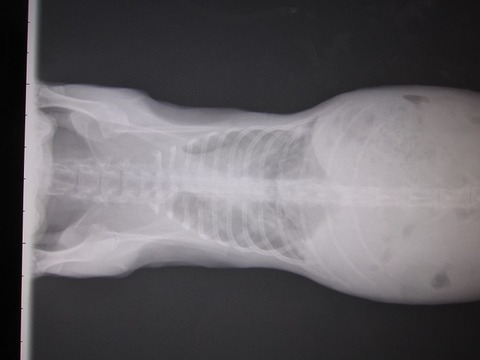

3月26日(金)病院 1.30kg

折り返して減ってきてる予想だったのに増えてて…

朝の掃除で糞が少なく感じたから、出る方が悪かったからとか???

この日は切歯の処置も。骨の歪みから伸びる方向も最初に比べると前へ、という感じ。

そして左側はもう処置をせんでも確定、かな。

排膿の処置、前後の違いはわかりづらいか…。

膿だけでなく空気(気泡)も出てくると。

繋がってるであろう口から空気が入ったか、

膿自体から発生するガスか、ここらで抗生剤の種類を変えることに。

振り返って見比べるとこの数カ月のことだのに、

確実に膿の範囲と骨の変形が広く大きくなってる。

…見た目的にはまだこれからもっと“かわいそう”になってくると思います。